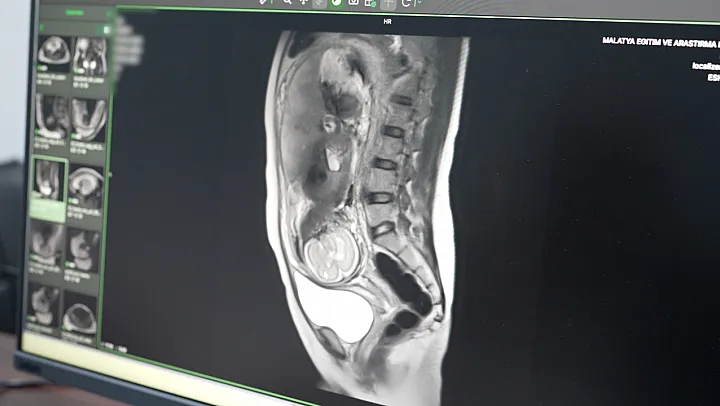

Hastanenin teknolojik atağı sadece kalp sağlığıyla sınırlı kalmadı. Daha önce yalnızca büyükşehirlerdeki tam teşekküllü merkezlerde yapılabilen 'Multiparametrik Prostat MR' ve 'Kardiyak MR' gibi özellikli işlemler artık Malatya'da rutin hale geldi. Özellikle anne adaylarını yakından ilgilendiren Fetal MR uygulamasıyla, anne karnındaki bebeklerin gelişimsel süreçleri ve olası anomalileri detaylıca incelenebiliyor. Bu yöntem, doğum öncesi planlamaların çok daha sağlıklı yapılmasına imkan tanıyor.